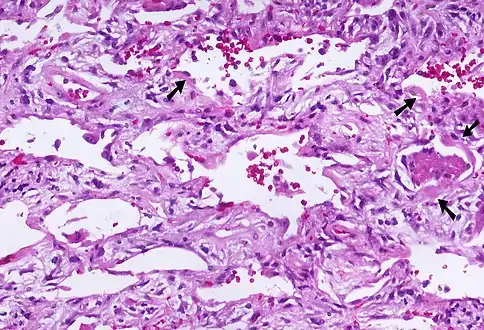

| Micrograph of diffuse alveolar damage, the histologic correlate of acute interstitial pneumonitis. H&E stain. | |

Rapid progression from initial symptoms to respiratory failure is a key feature. An X-ray that shows ARDS is necessary for diagnosis (fluid in the small air sacs (alveoli) in both lungs). In addition, a biopsy of the lung that shows organizing diffuse alveolar damage is required for diagnosis. This type of alveolar damage can be attributed to nonconcentrated and nonlocalized alveoli damage, marked alveolar septal edema with inflammatory cell infiltration, fibroblast proliferation, occasional hyaline membranes, and thickening of the alveolar walls. The septa are lined with atypical, hyperplastic type II pneumocytes, thus leading to the collapse of airspaces. Other diagnostic tests are useful in excluding other similar conditions, but history, X-ray, and biopsy are essential. These other tests may include basic blood work, blood cultures, and bronchoalveolar lavage. The clinical picture is similar to ARDS, but AIP differs from ARDS in that the cause for AIP is not known.